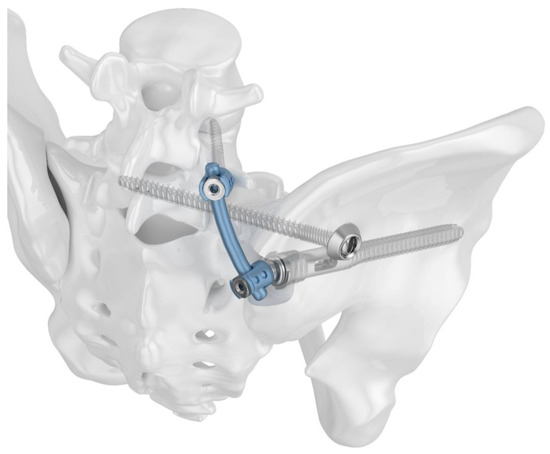

Figure 3.

Radiographs in two planes of the triangular fixation system with the sacroiliac screw positioned through the fenestra of the iliac screw.